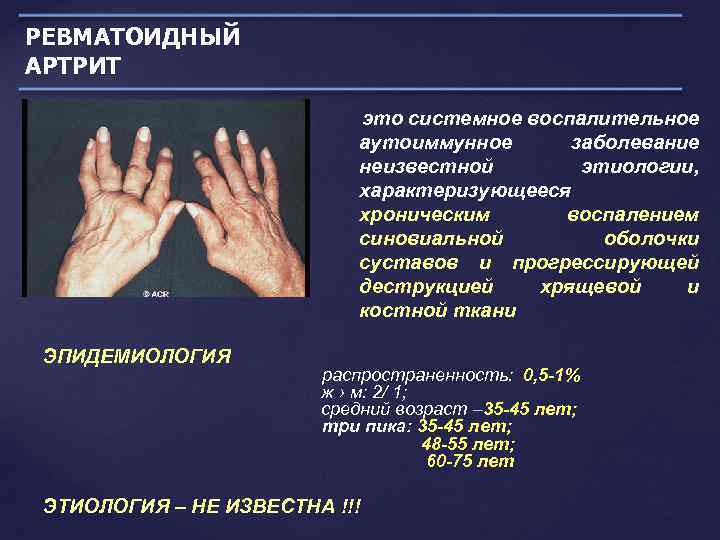

РЕВМАТОИДНЫЙ АРТРИТ это системное воспалительное аутоиммунное заболевание неизвестной этиологии, характеризующееся хроническим воспалением синовиальной оболочки суставов и прогрессирующей деструкцией хрящевой и костной ткани ЭПИДЕМИОЛОГИЯ распространенность: 0, 5 -1% ж › м: 2/ 1; средний возраст – 35 -45 лет; три пика: 35 -45 лет; 48 -55 лет; 60 -75 лет ЭТИОЛОГИЯ – НЕ ИЗВЕСТНА !!!

РЕВМАТОИДНЫЙ АРТРИТ это системное воспалительное аутоиммунное заболевание неизвестной этиологии, характеризующееся хроническим воспалением синовиальной оболочки суставов и прогрессирующей деструкцией хрящевой и костной ткани ЭПИДЕМИОЛОГИЯ распространенность: 0, 5 -1% ж › м: 2/ 1; средний возраст – 35 -45 лет; три пика: 35 -45 лет; 48 -55 лет; 60 -75 лет ЭТИОЛОГИЯ – НЕ ИЗВЕСТНА !!!